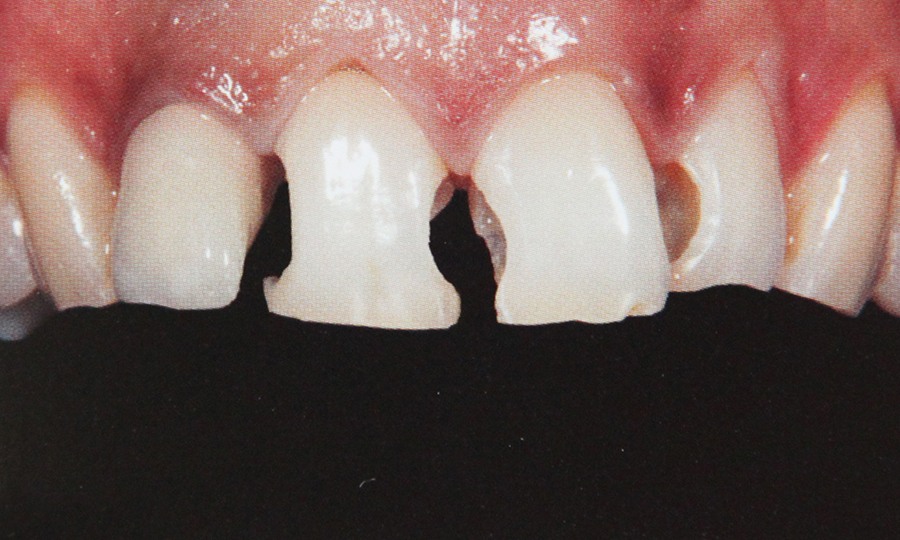

Tehnicile adezive directe de lucru cu materiale bazate pe rasini composite reprezinta o modalitate excelenta de restaurare estetica si minim invaziva a dintilor frontali. Obtinerea rezultatelor estetice asteptate este legata indesolubil de alegerea si utilizarea corecta, conform indicatiilor, a materialelor si tehnicilor de lucru adecvate, fiecarei situatii clinice.

Se ocupa cu tratarea leziunilor carioase ale dintilor precum si a celor necarioase care pot fi fracturi, distrofii sau leziuni de uzura dentara.

Tratamentul cariei urmareste:  - indepartarea tesuturilor dentare afectate

- protectia tesuturilor sanatoase

- recostructia dintelui (plomba) cu ajutorul unor materiale care asigura in egala masura rezistenta,

functionalitatea si estetica.